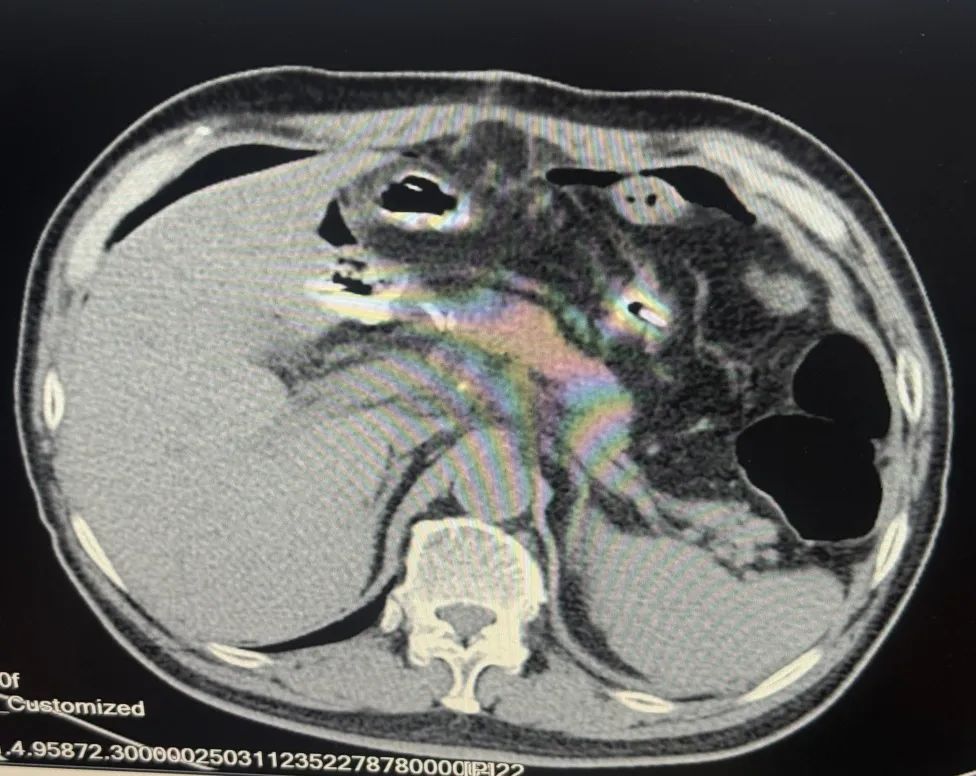

内容提要 从盘锦到葫芦岛,跨越180公里的生命接力中,葫芦岛市第二人民医院胃肠外科刘万忠主任团队用精准的治疗方案和手术技术,为晚期胃癌患者点燃了新的生命希望。 Part.01 隐秘的危机 从食欲骤降到癌魔突袭 2024年深冬,一向健朗的张大爷突然茶饭不思,短短半月暴瘦12斤。胃镜图像触目惊心:食管下段至胃窦广泛紫红色病变、胃壁僵硬、胃底后壁近贲门见不规则隆起溃疡性病变,表面污秽苔及陈旧血痂附着。病理结果明确指向“胃低分化癌”,更令人担忧的是,增强MR显示癌细胞已经扩散到淋巴结,腹腔多发转移,这一结果更让病情雪上加霜。三次化疗未能遏制病情,子女们近乎绝望:“难道真的没有希望了吗?” 患者术前胃部影像 Part.02 从绝望到希望 两城辗转中的诊疗抉择 转机出现在葫芦岛亲戚的建议下:“来我们这儿的市二院看看吧,多看一家医院就多一份希望”。胃肠外科刘万忠主任仔细翻阅厚厚的检查资料后,向家人说出了自己的想法:“虽然病情复杂,但精准的手术干预仍有延续生命的希望。”这一判断像黑暗中的一束光,点燃了全家的希望。最终确定手术方案为“胃恶性肿瘤根治术(全胃切除伴食管空肠吻合术+空肠侧侧吻合术+区域淋巴结切除术)”。 Part.03 硬核技术权威支撑 手术台上的生死博弈 面对这个被多家医院判定“不可切除”的病例,刘万忠主任团队展现了区域顶尖医疗团队的实力:术中见肿瘤如蛛网般蔓延胃底胃体,侵蚀胃小弯及胃角,胃周可见肿大淋巴结,已浸及全层,与周围组织形成致密粘连。肿大淋巴结包绕重要血管,稍有不慎即引发致命性出血,既要彻底清除肿瘤,又要保留消化功能,这对吻合技术提出极限挑战。历经4小时鏖战,刘万忠主任团队不仅完整切除病灶,更通过精细的消化道重建,最大限度保留了患者术后生活质量。 术后第3天,张大爷已能经口进食米汤;两周后,他带着定制的营养食谱和康复管理手册出院。出院时,他紧握刘万忠主任的手哽咽道:“是你们给了我第二次生命!” 刘万忠主任深耕胃肠肿瘤领域近30年,已完成胃结直肠及肛肠等各类手术万余例,其中胃结直肠等三四级手术3000余例。在刘万忠主任带领下,科室已与中国医学科学院肿瘤医院、北京中日友好医院、中国医科大学附属第一医院、中国医科大学附属盛京医院、辽宁省肿瘤医院、锦州医科大学附属医院建立合作,可提供一站式专家看诊、手术及国内名院转诊服务。科室以胃及结直肠微创手术为特色,可开展多种疑难和高难手术,越来越多曾被视为“没希望”的患者,在这里找到了新生的可能。 Part.04 人民医院 人民名医 刘万忠 主任医师 硕士研究生 ·葫芦岛市第二人民医院胃肠外科主任 ·世中联盆底专业委员会委员 ·世中联虚实挂线委员会委员 ·中日友好医院肛肠专科医联体专家委员会委员 ·中国研究型医院学会腹膜后与盆底专业委员会青年委员 ·中国人体健康促进会甲状腺肿瘤专业委员会委员 ·辽宁省中西医结合肛肠委员会委员 ·东三省肠内外营养专业委员会委员 ·大连市中西医结合学会乳甲专业委员会常委 专业特色:从事胃肠肿瘤外科领域近三十年,在国内知名三甲医院担任普外科主任、学科带头人10余年。先后在中国医科大学附属二院、北京301医院、北京医科大学附属三院、中日友好医院、哈尔滨医科大学附属二院进修学习。擅长胃癌、结直肠癌、胃肠间质瘤等胃肠肿瘤及肛肠复杂疾病诊治。 精通普外科腹腔镜微创技术、独立开展普外科腹腔镜手术包括:腹腔镜阑尾切除术(LA)、腹腔镜疝修补术(TAPP)、腹腔镜结直肠癌根治术及腹腔镜直肠癌NOSES手术等高难度手术,已完成胃结直肠及肛肠等各类手术万余例,其中胃结直肠等三四级手术3000余例。主持吴阶平基金会科技部《FH检测技术在直肠癌超早期筛查中的临床意义》临床科研课题项目一项。在国内外行业杂志发表论文10余篇,参与编撰专著2部。